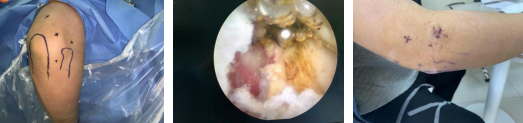

术前(左图)关节镜探查(中图)术后(右图)

通过肘关节镜微创手术治疗后,患者肘关节疼痛减轻,工作时不再受疼痛折磨。